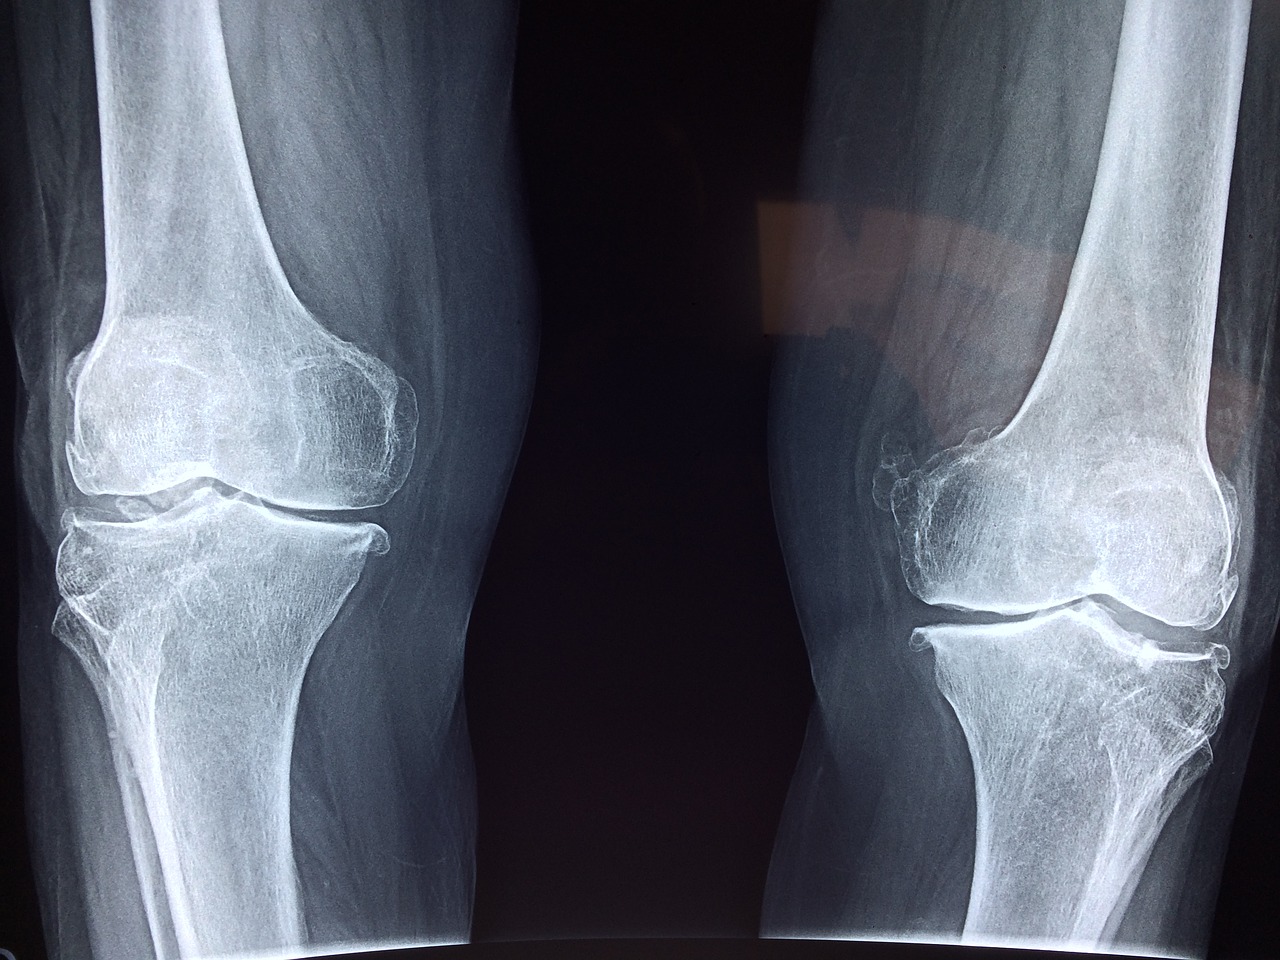

The Riverside Company has continued its flurry of Asia-Pacific exits over the past 12 months by selling Global Orthopaed